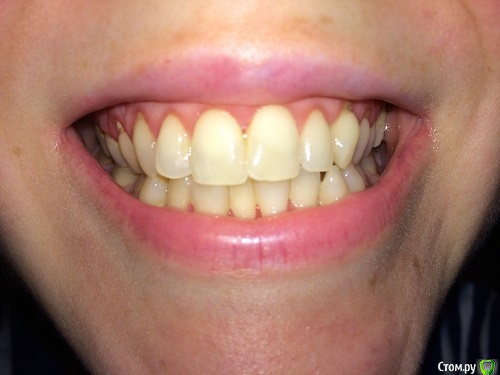

lalafa Опубликовано 16 августа, 2017 Поделиться Опубликовано 16 августа, 2017 (изменено) Здравствуйте, помогите, пожалуйста, советами.Мне 29 лет. Хронические заболевания - гранулезный фарингит, гастрит, ГЭРБ, сколиоз. У меня генерализованная рецессия десны, катаральный гингивит, пародонтальных карманов нет. Рекомендовано ортодонтическое лечение. НО ортодонты предупредили, что велика вероятность продолжения рецессии десны во время лечения и ухудшения ситуации. Посетила 2 пародонтологов, мнения противоположные. Один рекомендует операцию по закрытию рецессии методом пересадки трансплантата с неба. Хочет оперировать до ортодонт лечения самые проблемные зубы - клыки на нижней челюсти и 4ку. Мотив - утолщить десну, чтобы она выдержала брекеты и не рецессировала еще больше.Другой пародонтолог говорит, что так как именно эти зубы "не стоят в зубной дуге" (цитата врача) трансплантат с неба не приживется и результата не будет. Советует делать операцию после снятия брекетов на прямые зубы.Вопросы:1) Насколько в принципе опасно при такой рецессии проводить ортодонтическое лечение? зубы могут расшатываться и выпасть в процессе лечения?2) Закрывать рецессию до брекетов или после? Действительно, на таких вывернутых зубах не приживается трансплантат?3) Постоянно мучаюсь с катаральным гингивитом. Прохожу Проф чистку раз в 6 месяцев, но без толку. за чистотой слежу и самостоятельно, но скученные зубные ряды все равно провоцируют гингивит. Можно надеяться, что после брекетов гингивит вылечится? Изменено 16 августа, 2017 пользователем lalafa Ссылка на комментарий

lalafa Опубликовано 17 августа, 2017 Автор Поделиться Опубликовано 17 августа, 2017 Про гигиену чищу зубы как показал стоматолог, по схеме.Нитью больно пользоваться, потому что сильная скученность.После проф чистки гингивит все равно есть, просто десны не кровоточат, но они красные и припухшие. фото сделаны после недели применения ополаскивателя, от которого сильно желтеют зубы, поэтому такой вид, как будто проблемы с гигиеной.Скажите. пожалуйста, на снимке есть признаки пародонтоза? Ссылка на комментарий